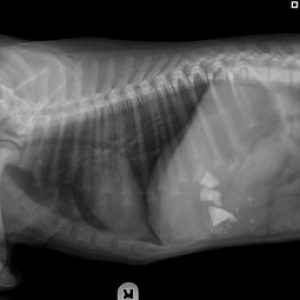

Pica in Dogs Stones from an xray in a puppy at The Andys Veterinary Hospital Dogs especially puppies love to...

Bladder stones in dogs and cats These are stones which vary in size from being microscopic sandy particles to large...